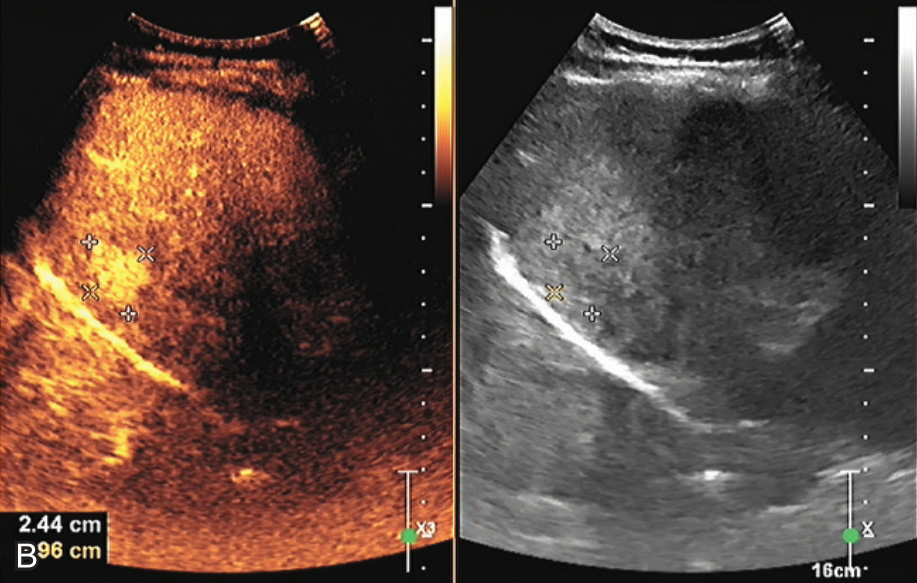

图1-5-2(续)

B.门脉期始终呈高增强;C.延迟期始终呈高增强